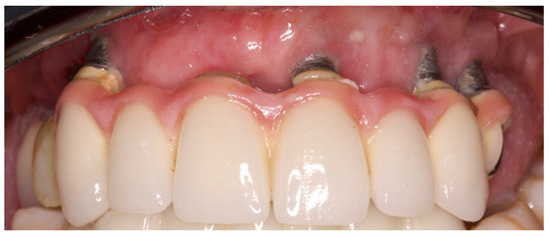

Retrospective Study of the Association between Peri-Implantitis and Keratinized Mucosa

- The presence of KM around the implants seems to have been associated with peri-implantitis and with a transparency of the peri-implant tissues.

- The absence of KM appears to have an impact on certain clinical parameters: Recession is augmented in implants with absence of KM; hygiene is facilitated when implants are surrounded by KM, therefore the plaque index is lower; probing depth tends to increase in implants without KM; bleeding and suppuration are reduced in the presence of KM and bone level tends to be lower in implants without KM.